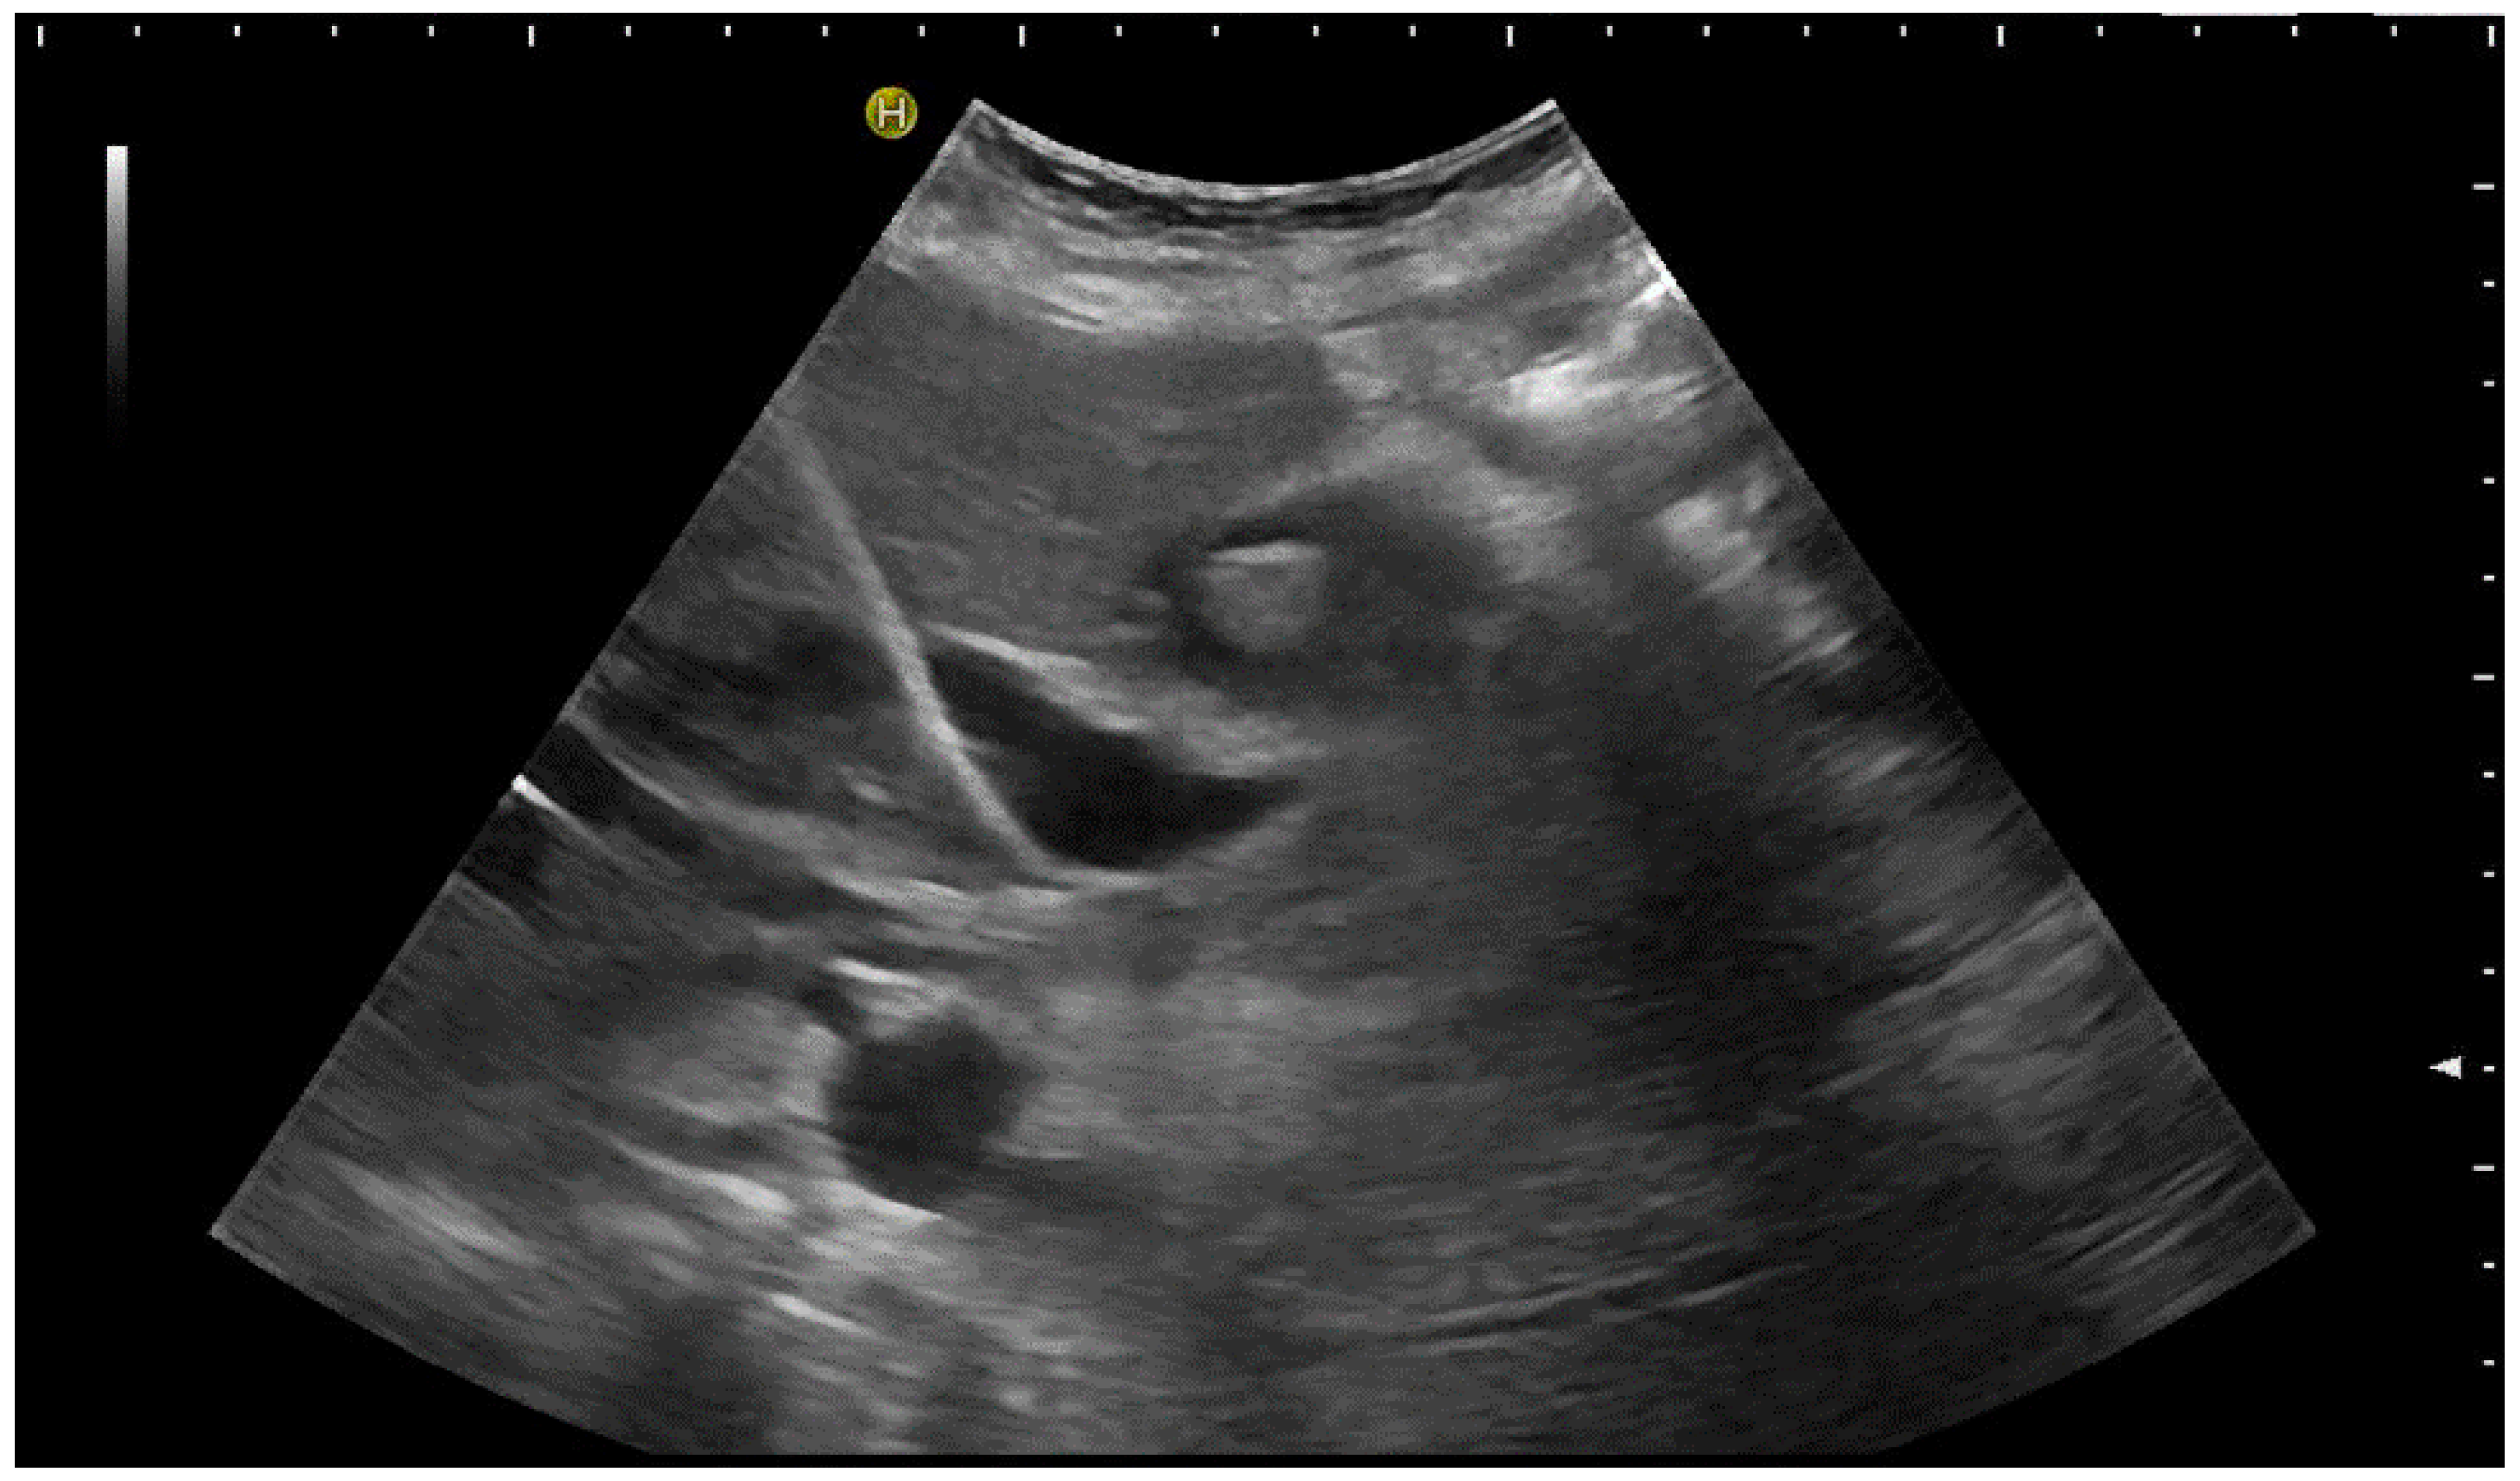

Again, the “in plane” approach is recommended to depict the needle in real time and continuously on its way. This is mandatory because iatrogenic perforation of the posterior gallbladder wall must be avoided. Both the drainage techniques, Seldinger (Figure 11a–c) and trocar (direct puncture, cf. Figure 10), may be used, depending on the physician’s preferences [43,58].

When using the Seldinger technique, first a Chiba needle is placed in the gallbladder (a), through which a 0.035” guide wire with bended tip is inserted (b). Plastic pigtail drainage (c) is then advanced over the guide wire.

We recommend the use of 8F or 10F pigtail drainage. If it is inserted using Seldinger’s technique, dilatation is not necessary. If the guide wire is confirmed to be in the correct place and is secured well, drainage placement can be performed without US visualisation [43,76].

As tube displacement is a relevant problem, we recommend the use of thread-locked catheters, which are supposed to keep the pigtail in its curled shape, thereby preventing dislocation.